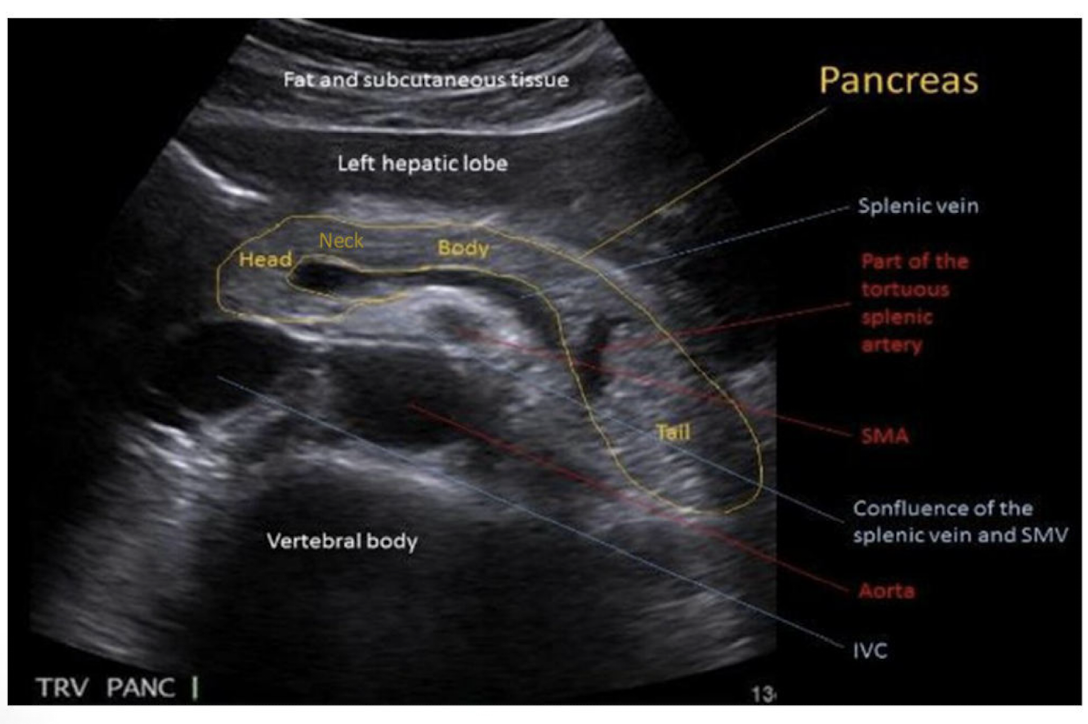

Be able to identify this image taken in a transverse plane

The pancreas sits horizontally in the abdominal cavity so in order to get a long axis image the sonographer must scan in the __________ plane

Transverse

What are the five sections of the pancreas?

1) Uncinate Process

2) Head

3) Neck

4) Body

5) Tail

label

identify all structures

A) left liver lobe

B) gastroduodenal artery

C) common bile duct

D) Main portal confluence

E) Splenic vein

F) SMA

G) IVC

H) Aorta